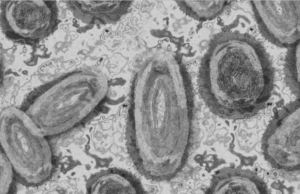

López Gatell confirma el segundo caso de viruela de mono en...

El subsecretario de Prevención y Promoción de la Salud, Hugo López-Gatell, confirmó un segundo caso de viruela del mono en la Ciudad de México.